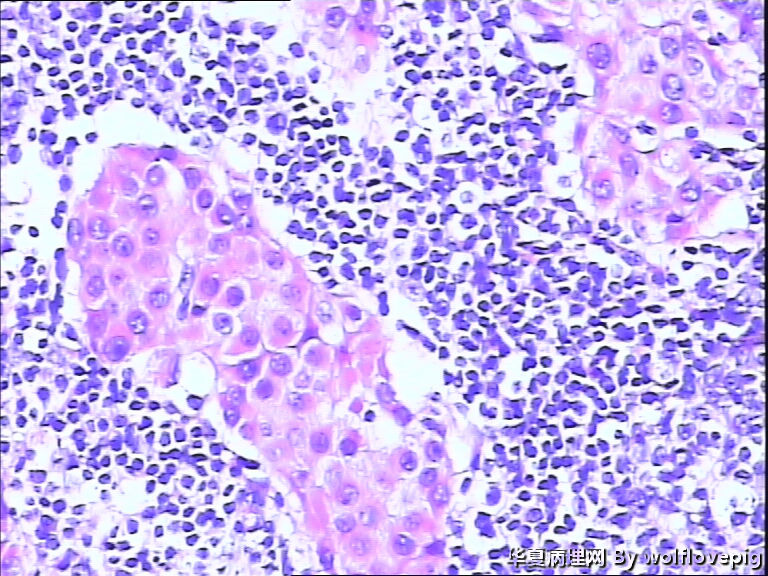

女,60y,发现右乳包块6+月。

灰白不整形组织一块:3*2*1.5cm,切面有一灰白区域,边界欠清,质韧。

标签:乳腺浸润性癌

浸润性癌。

浸润性导管癌,最好标记肌上皮。

浸润性导管癌

浸润性导管癌,分化差,除外混合癌(导管癌+小叶癌),免疫组化证实。(本例图像很多,局部炎症反应重,瘤细胞还成合体样无腺管形成似髓样癌,局部似炎性乳癌,局部似小叶癌,呵呵)